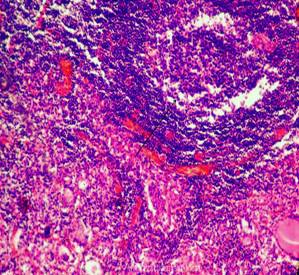

В одном из практических случаев мы столкнулись с сочетанием аутоиммунного зоба Хасимото и склерозирующего зоба Риделя: обширные поля разрастания грубой фиброзной ткани сочетались с крупными очагами густой круглоклеточной (лимфоидной) инфильтрации. Ткань щитовидной железы практически не прослеживалась, в отдельных полях зрения были видны резко сморщенные группы фолликулов (вернее то, что от них осталось; стрелки).

Рис. 14-17. Сочетание зоба Хасимото и зоба Риделя. Окраска: гематоксилин и эозин. Увеличение х100 х250.